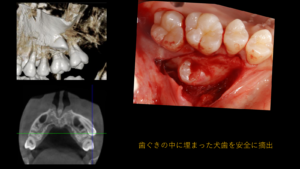

上顎に乳歯が残存しており本来生えてくるはずの犬歯が埋伏し、さらに下顎の小臼歯が破折といった、複数の問題を抱えたケースでした。

・埋伏犬歯の外科的処置・乳歯の抜去・下顎小臼歯の抜歯・上下ワイヤー矯正

・埋伏犬歯への対応と歯の役割の再設計 本症例では、埋伏している犬歯を摘出したため、